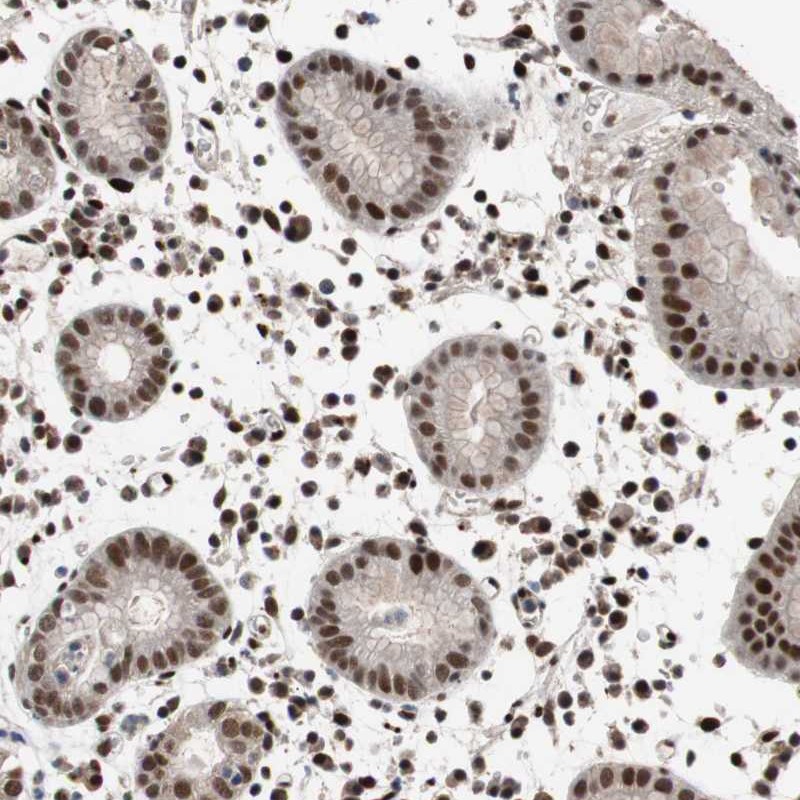

Immunohistochemical staining of human stomach shows strong nuclear positivity in glandular cells.